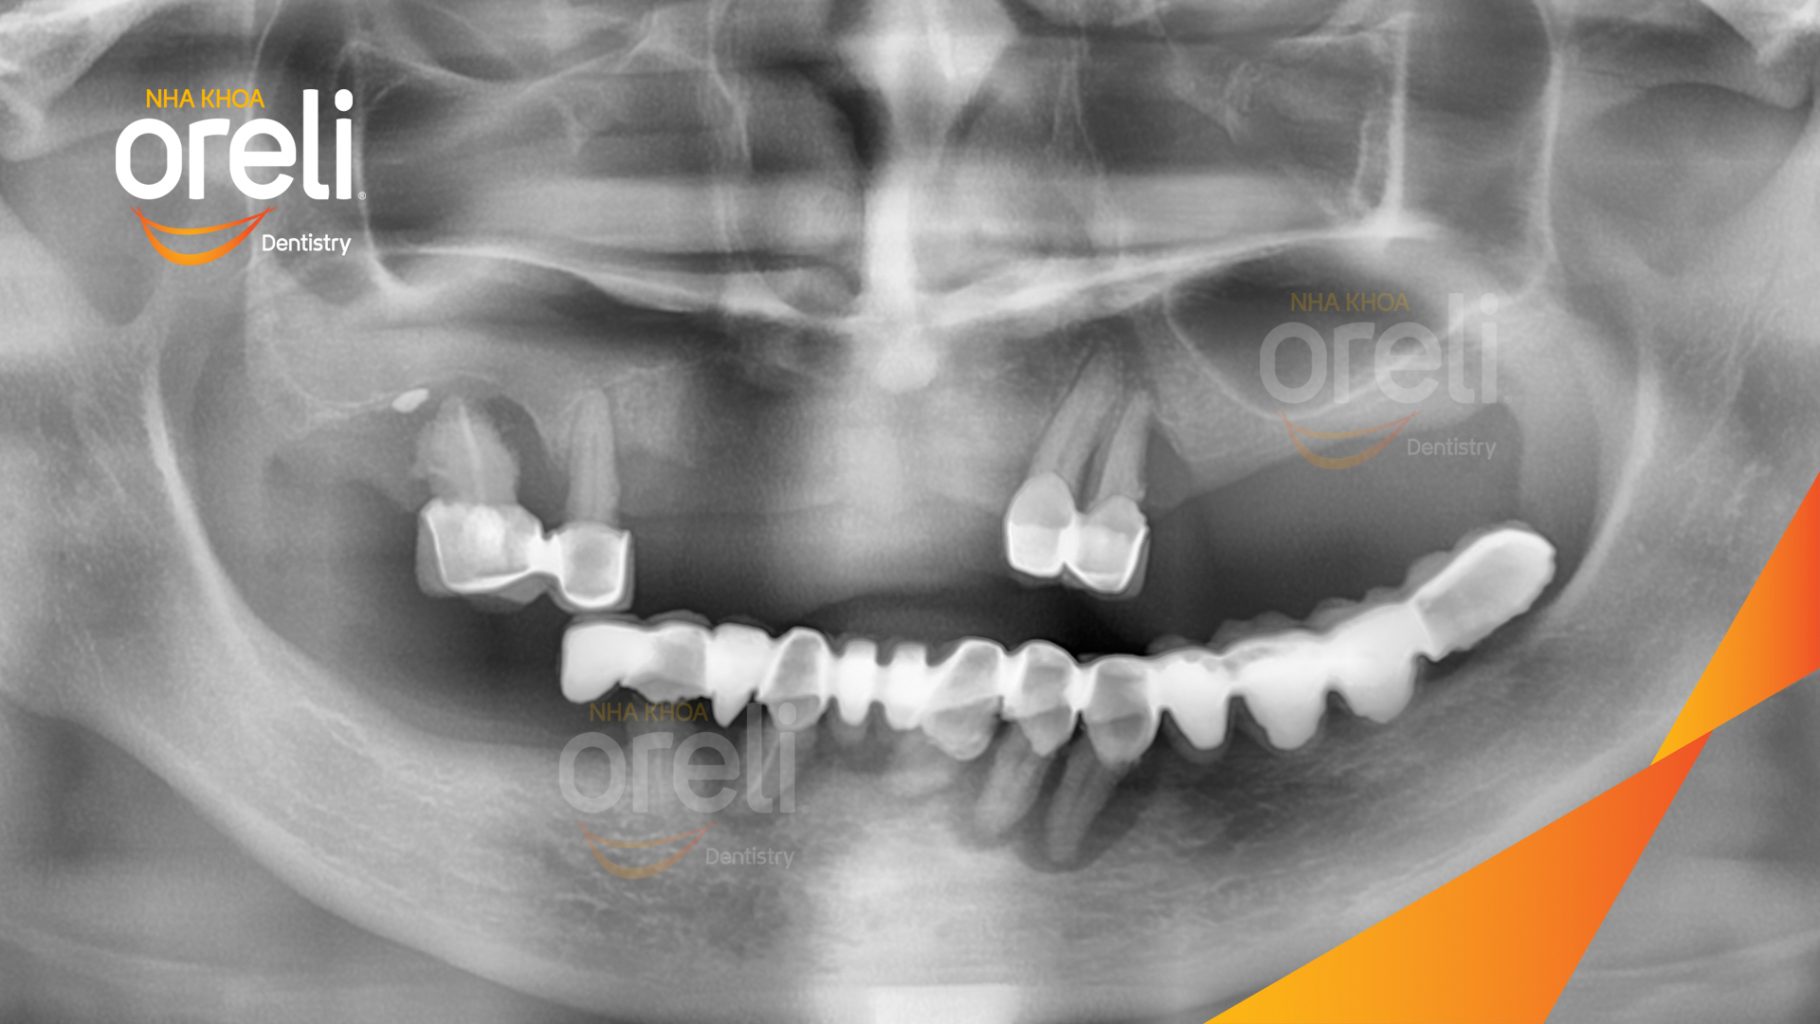

Tình trạng: Cầu răng sứ lâu ngày, tiêu xương nhiều ở cả hàm trên và dưới

Giải pháp: Cắt bỏ cầu sứ nhổ răng lung lay, cấy ghép răng implant hàm trên và dưới

Hình ảnh thực tế